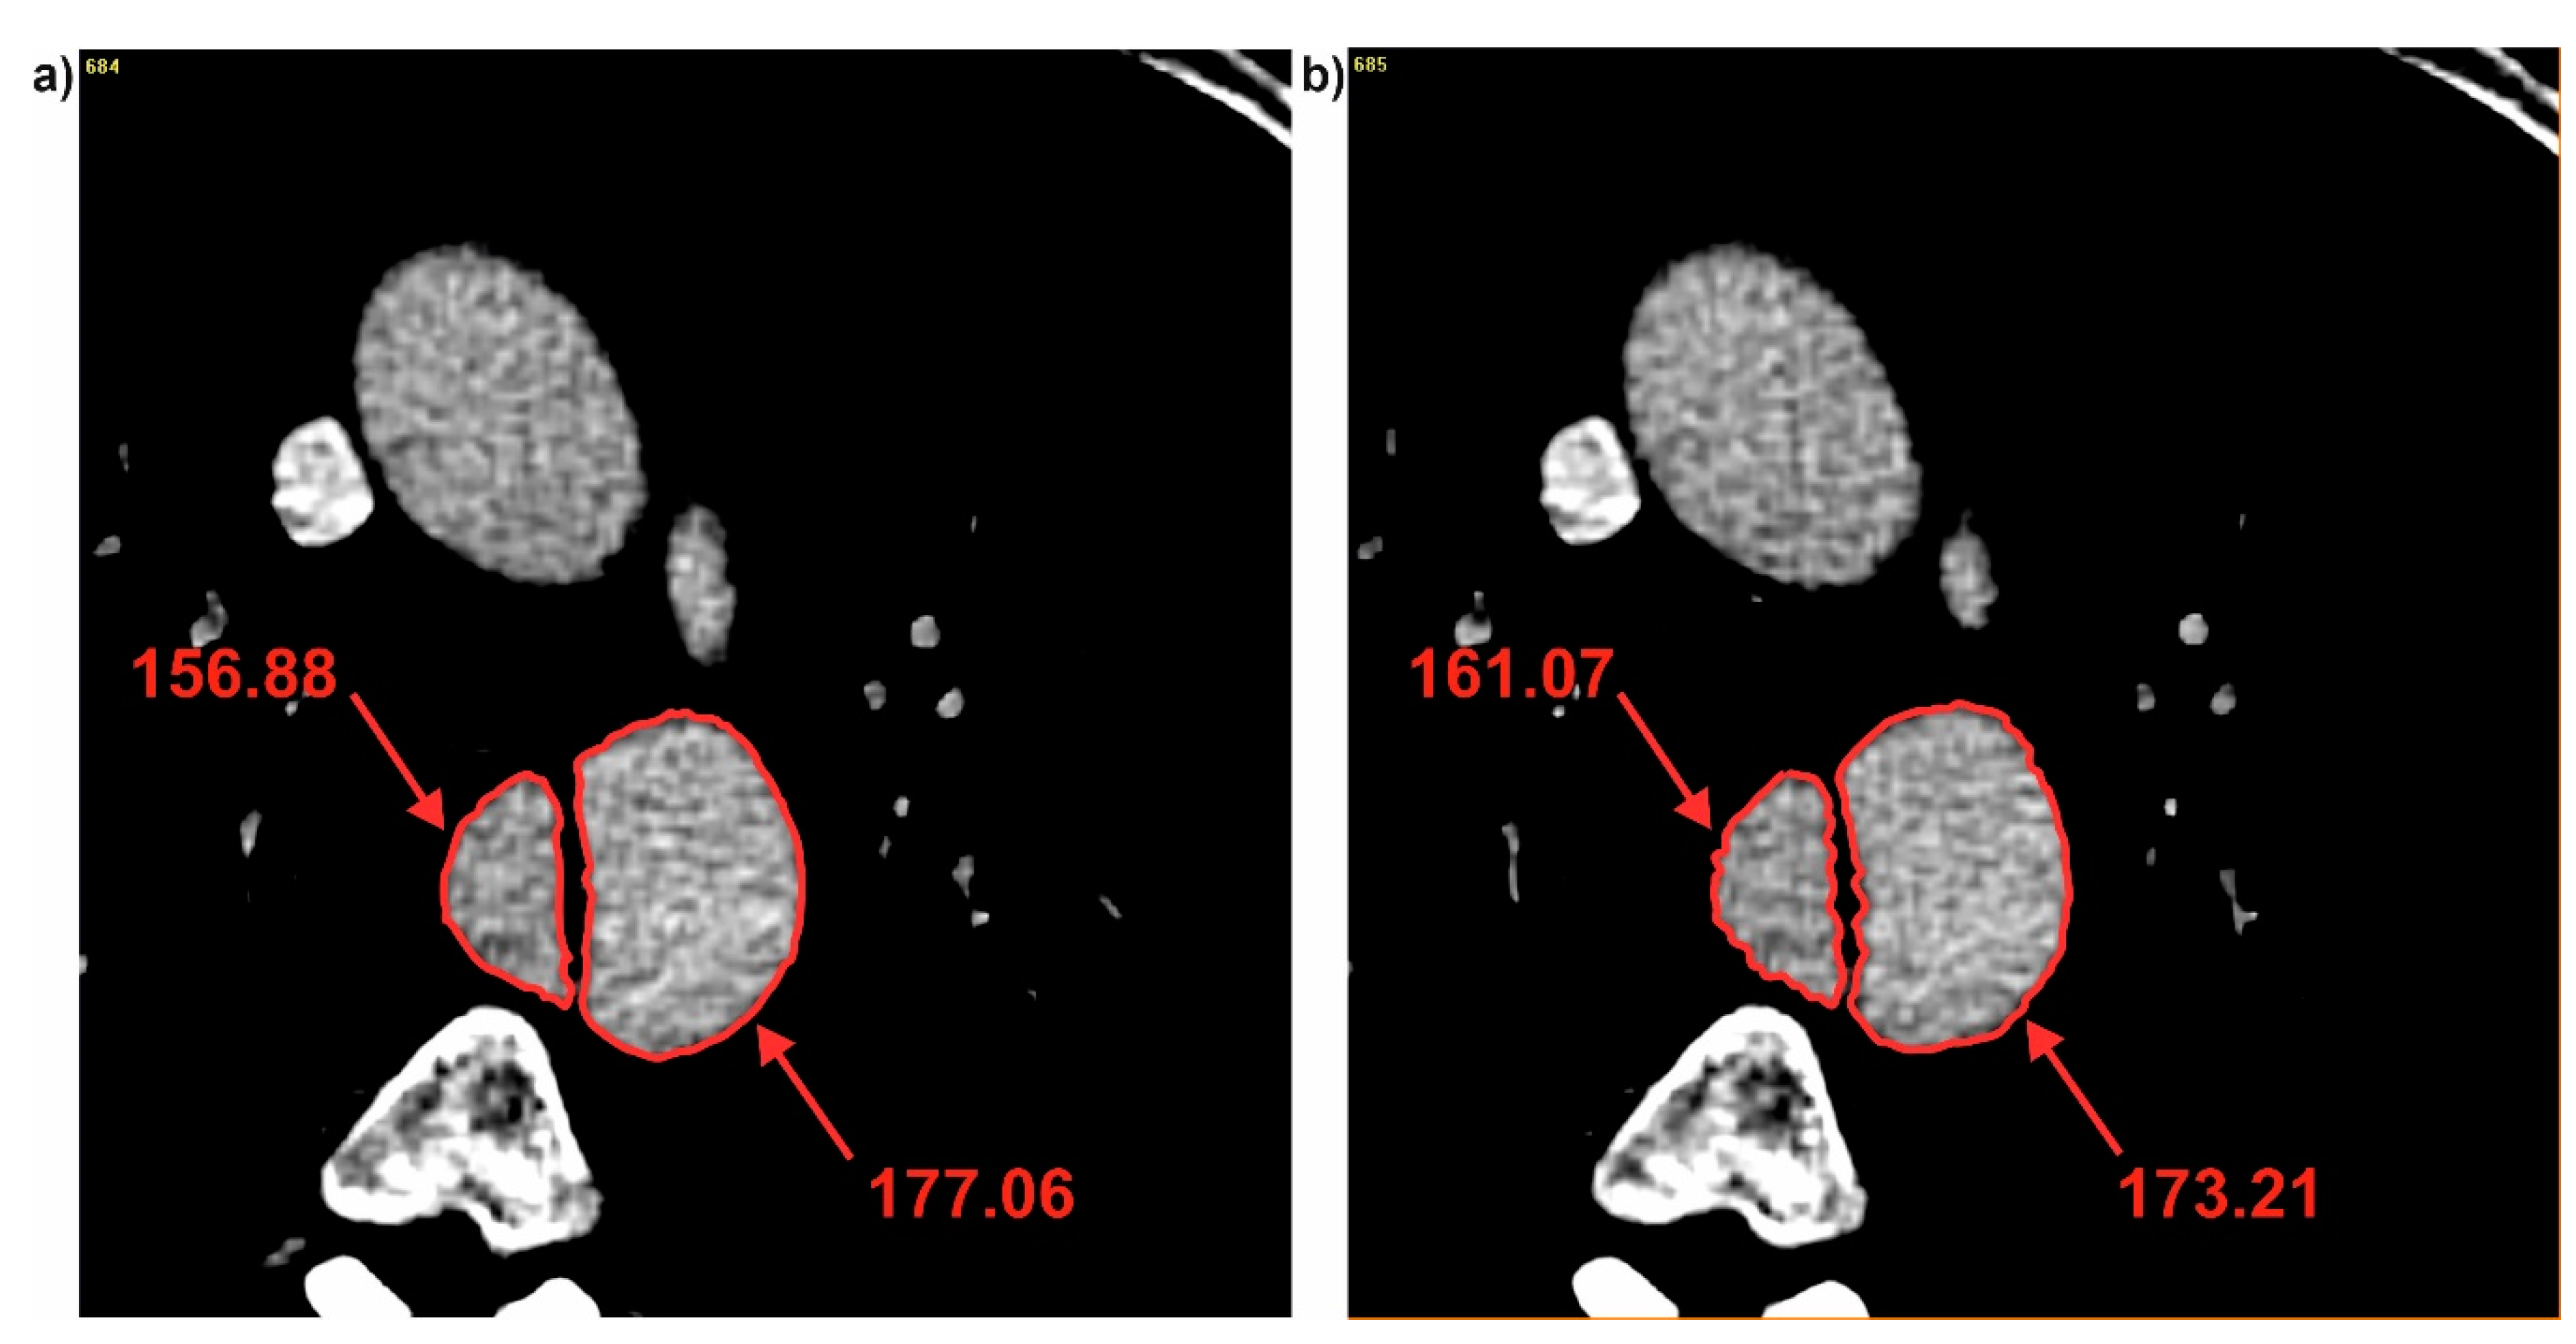

Next, brightness value for each cross-section for all three patients was analyzed. It was observed that with decrease of diameter, brightness value increased for the common duct for both DF and DHy (Figure 5). For P1 decrease of diameter was from 49.27 to 47.37 (calculated for DF) and from 43.62 to 43.08 (calculated for DHy) indicating an increase of brightness value from 161.51 to 164.81 for the common duct (for cross-section 3 and 4) (Figure 6). Similar trend was observed for the true and false ducts. Decrease of diameter for P1 for the false duct was from 26.65 to 20.80 (calculated for DF) and from 19.35 to 17.99 (calculated for DHy) indicating an increase of brightness value from 156.88 to 161.07 (for cross-section 11 and 12) (Figure 7a). While for the false duct a decrease of diameter for P1 was from 32.70 to 35.78 (calculated for DF) from 33.16 to 36.50 (calculated for DHy) indicating an increase of brightness value from 177.06 to 173.21 (for cross-section 11 and 12) (Figure 7b).

Figure 7. Brightness of true and false ducts for P1: (a) Cross-section number 11 and (b) cross-section number 12. Values of brightness were calculated in Pixels.